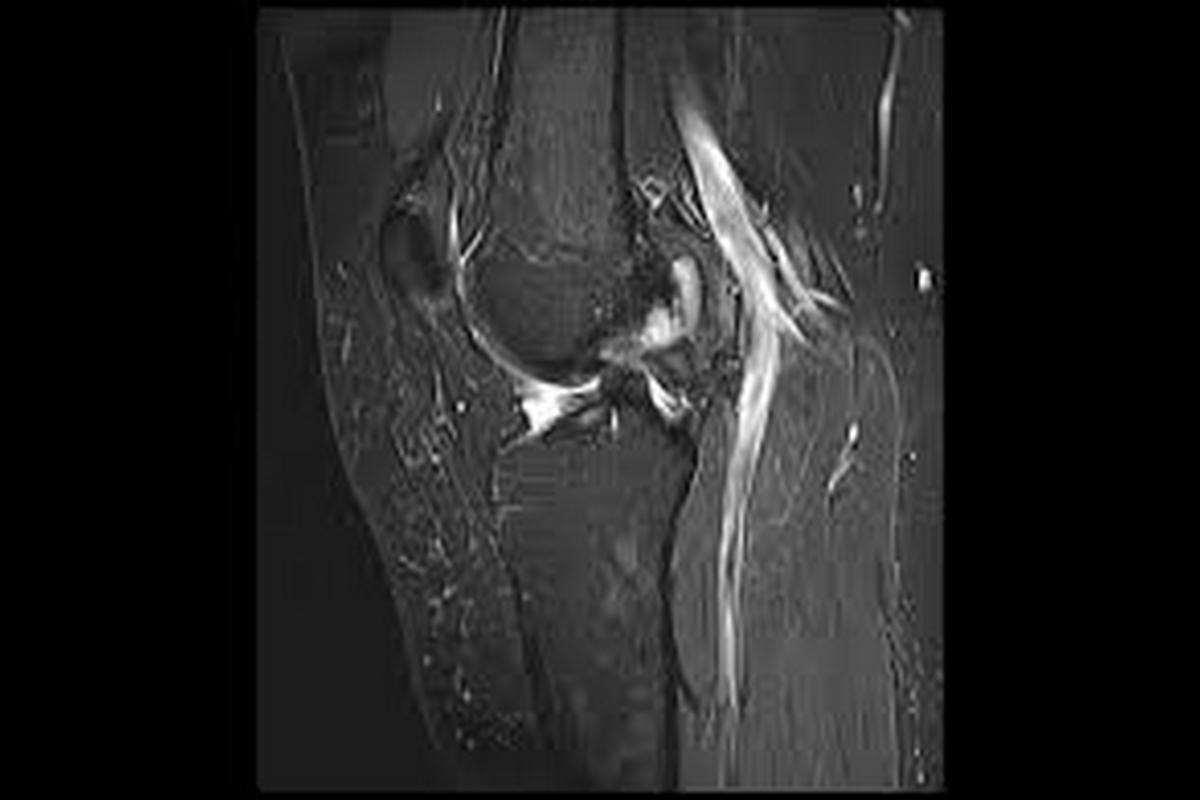

Ακτινογραφίες για αποκλεισμό οστικών κακώσεων

Μαγνητική τομογραφία (MRI), που επιβεβαιώνει τη ρήξη πρόσθιου χιαστού και αναδεικνύει συνοδές βλάβες σε μηνίσκους, χόνδρο ή πλάγιους συνδέσμους

Η MRI αποτελεί την εξέταση εκλογής για την τεκμηρίωση της βλάβης.